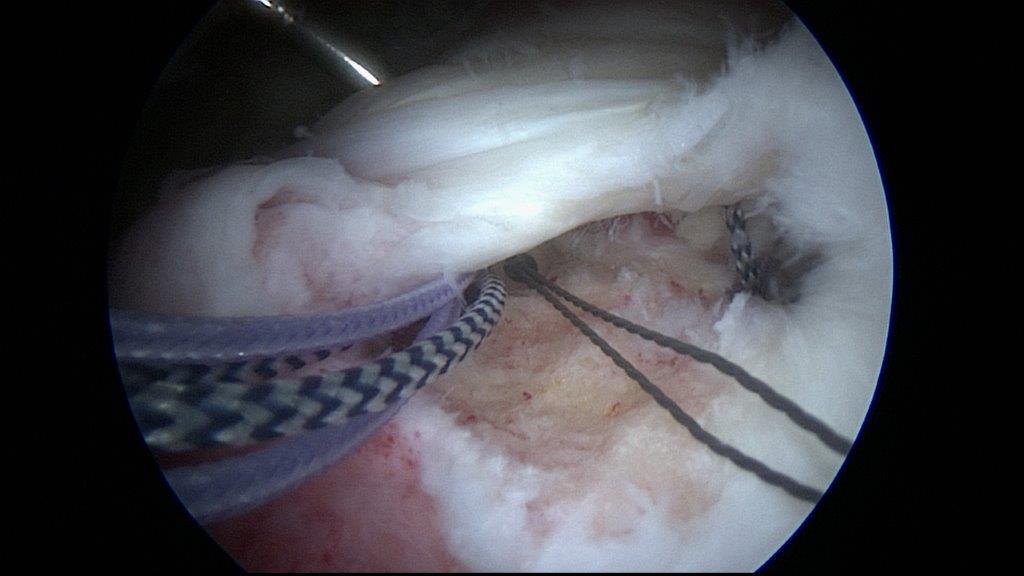

• Arthroskopische Sehnenrekonstruktion „ Schlüsselloch-Chirurgie“

Die Operation in und um das Gelenk wird über kleine Inzisionen von ca. 1 cm mit Hilfe einer dünnen Stabkamera in Videotechnik durchgeführt. Das Gelenk wird mit Wasser aufgefüllt und über weitere kleine Inzisionen werden Instrumente in das Operationsfeld gebracht.

Nähen des Risses während der Arthroskopie